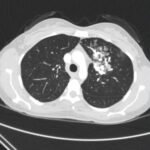

Hemoptysis is a common presenting symptom of hereditary hemorrhagic telangiectasia (HHT), an often overlooked diagnosis in the emergency setting. Patient history often includes telangiectasias, epistaxis, visceral lesions, and a family history of similar findings. Here, we review a case of HHT in a young woman, presenting initially with hemoptysis. Imaging was significant for large left upper lobe arteriovenous malformation (AVM), requiring patient admission and interventional radiology embolization of the AVM. The purpose of this report is to highlight a diagnosis that is important not to miss in the emergency department.

Pulmonary arteriovenous malformation, hereditary hemorrhagic telangiectasia, Osler-Weber-Rendu syndrome.